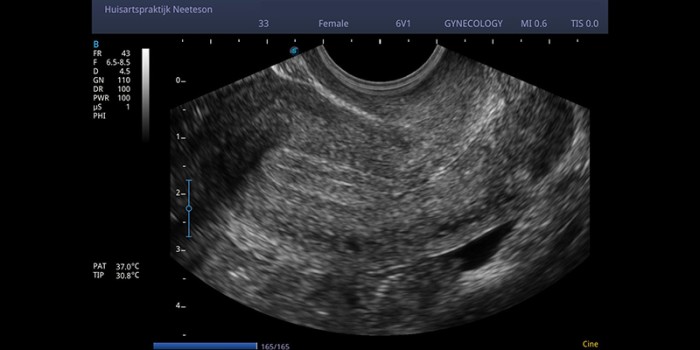

Transvaginale echo uterus

Transvaginale echo van een uterus.

© Huisartspraktijk Neeteson